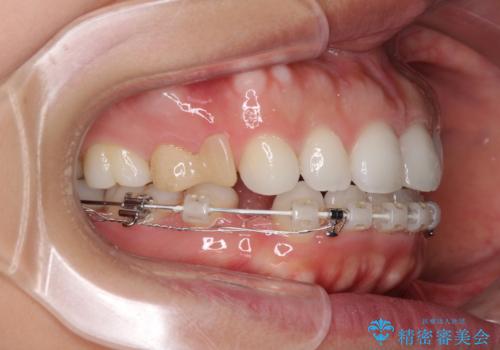

- 矯正装置

- ハーフリンガル

表側のワイヤー矯正に比べると治療期間は長く、費用も高額となりますが、どうしても目立たせたくないという方にはお勧めの抜歯矯正です。